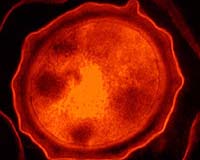

Shown here is an electron micrograph of a Bacillus anthracis spore, magnified 92,000 times. Credit: University of Michigan/ Journal of Bacteriology

Bacillus anthracis can quickly transform from a dormant spore (the white powder sent to U.S. lawmakers and others in the mail in 2001) into an active, quickly-multiplying organism once it gets inside the warm lungs of a host. Bacillus anthracis can cause infection elsewhere in the body, but is most serious and potentially deadly when its spores are inhaled.